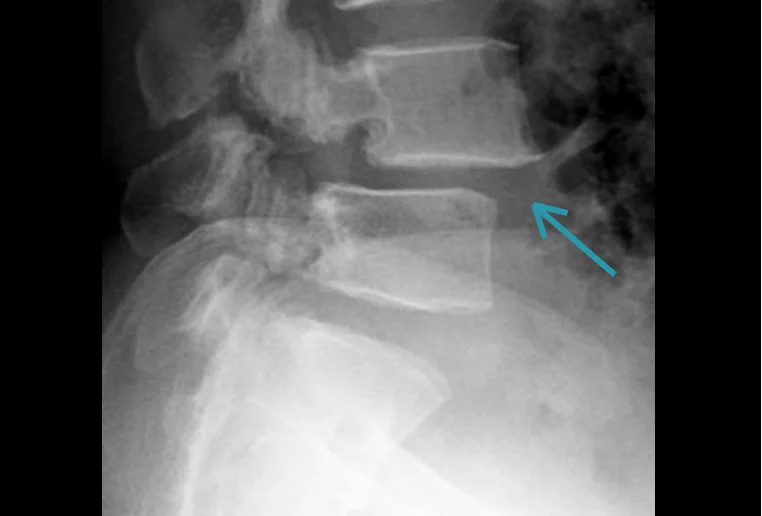

Lumbar spine X-ray showing grade I–II spondylolisthesis at L4–L5 with mild vertebral slippage.

Lumbar spine X-ray – spondylolisthesis L4–L5, grade I–II. Courtesy of The Radswiki, Radiopaedia.org. Slučaj rID: 11967